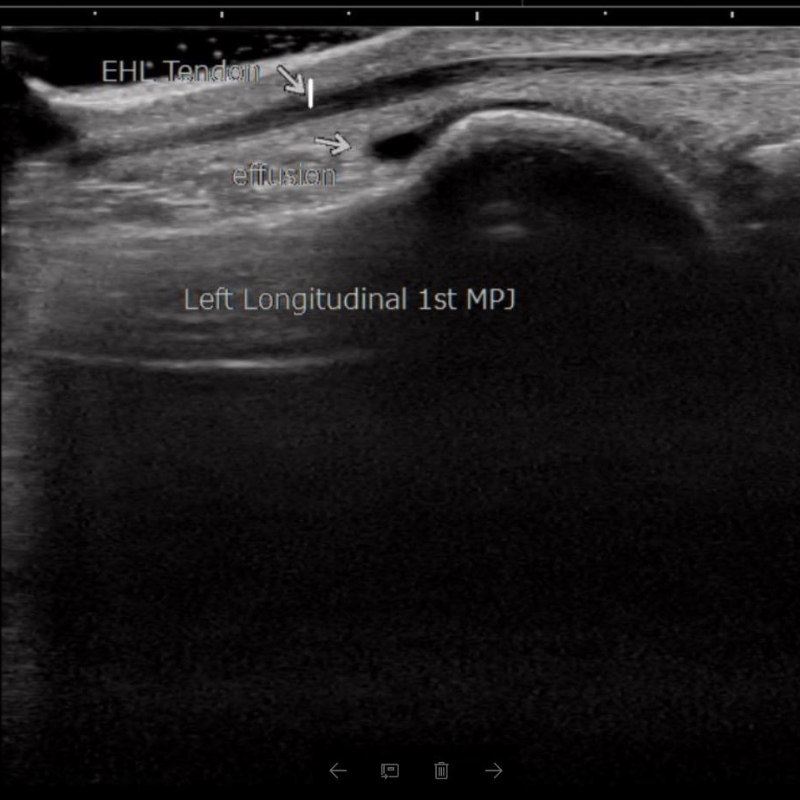

Diagnostic ultrasound works much like the device used during pregnancy to capture images of a baby in the womb. In podiatry, we use this safe, non-invasive tool to see tendons, ligaments, joints, and even bone in real time. Unlike X-rays or MRIs, ultrasound allows our podiatrists to gently move and stress your joints during the scan, giving a more complete understanding of what’s causing your pain.

Our podiatrists use diagnostic ultrasound to evaluate a wide range of conditions with precision and accuracy.

• Cysts and bursitis

• Inflammatory conditions

Beyond diagnosis, ultrasound also guides treatment. If a problem area is identified, our podiatrists can use live imaging to precisely deliver therapies, including steroid injections, amniotic tissue allografts, platelet-rich plasma (PRP), or shockwave treatments directly to the site of injury.